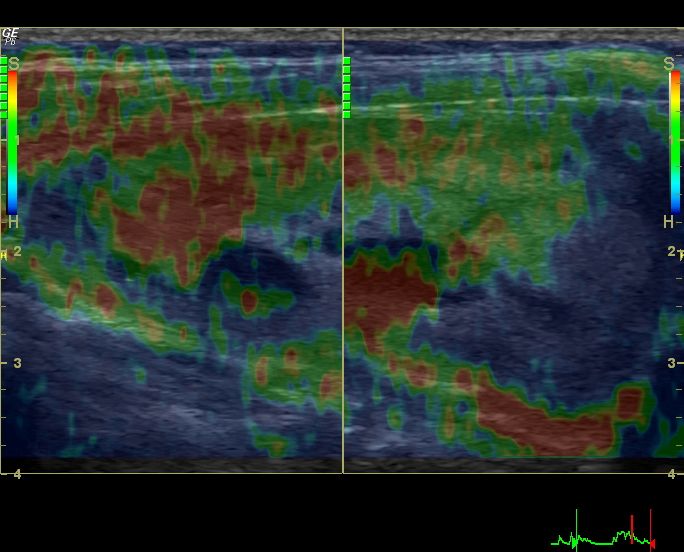

Sonography- retained products of conception

A few days after delivery, this patient still has hemorrhagic discharge per vagina. Ultrasound imaging of the uterus show what appears to be echogenic matter within the uterine cavity.

This tissue in the uterine cavity (retained products of conception) shows no vascularity on Doppler study. This matter could represent decidual remnants or even bits of placental tissue.